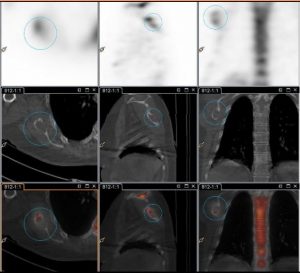

Il existe des lésions lytiques au niveau de la scapulaire droite et du bord gauche du sacrum peu visibles sur l’examen balayage corps entier.

Les acquisitions SPECT CT permettent de les mettre en évidence.

Intérêt majeur de la SPECT CT dans les bilans d’extension, en particulier dans les situations à risque de métastases osseuses essentiellement lytiques.

– Il existe tout au plus une image en cocarde du bord latéral de l’omoplate droite.

Image de la scapula droite suspicieuse et du sacrum latéralisé à droite à minima (kyste de tarlov?).

Effectivement, le mode balayage est insuffisant ici, les lésions lytiques du bord gauche du sacrum et de la scapulaire droite peuvent ne pas être retenues sur la lecture de l’image corps entier.

Intérêt des acquisitions SPECT CT dans les bilans d’extensions (notamment si risque de métastases osseuses lytiques).